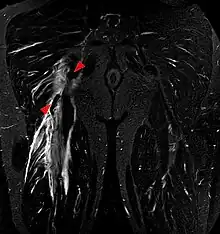

Tear of the hamstrings muscles at the ischial tuberosity seen on MRI (coronal STIR). The arrowheads indicate the tuber and the retracted tendon stump. Significant bleeding around and into the muscles.

Imaging the hamstring muscles is usually performed with an ultrasound and/or MRI.[9]  The biceps femoris is most commonly injured, followed by semitendinosus. Semimembranosus injury is rare. Imaging is useful in differentiating the grade of strain, especially if the muscle is completely torn.[10] In this setting, the level and degree of retraction can be determined, serving as a useful roadmap prior to any surgery. Those with a hamstring strain of greater than 60mm in length have a greater risk of recurrence.[11]